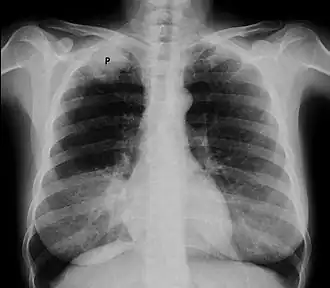

![]() Рентгенограмма органов грудной клетки, опухоль Панкоста (обозначена P, немелкоклеточная карцинома правого лёгкого) у курящей женщины 47 лет. | |